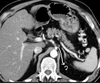

4

Q

Name the marked structure

A

Ascending colon

How well did you know this?

1

Not at all

2

3

5